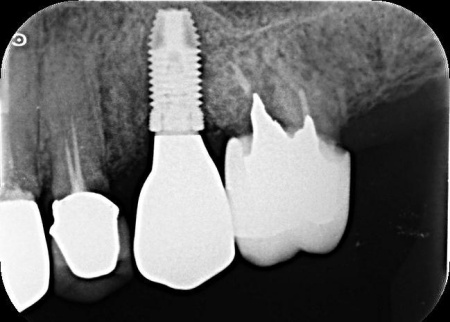

| 診断 | 拝見したところ、左上奥歯(第2小臼歯)1本が折れ、歯根だけの状態になっていました。 レントゲン撮影をして詳しく検査した結果、治療して温存することは困難な状態だったため、残っている歯根を抜き、欠損部分を補う治療が必要だと判断しました。 患者様は、人工歯根であるインプラントによる治療を希望されていましたが、レントゲン撮影の結果では、インプラントを入れるために必要な骨の量が足りていません。 以上のことから、まずは慎重に治療方法を検討する必要があると診断しました。 |

| 行ったご提案・治療内容 | 患者様には、折れた左上奥歯は温存ができず、歯根を抜く必要があることをお伝えしました。 そのうえで、希望されているインプラント治療を行うために必要な点を説明しています。 ・インプラント治療に必要な骨の量を確保するための「骨補填」を行う こちらに同意いただき、3ヶ月後からインプラント治療を始めることになりました。 まず、左上奥歯を抜きます。 3ヶ月後、顎の骨の状態が良好であることを確認し、インプラントを埋入する手術を実施しました。 |

治療前

治療中

治療後